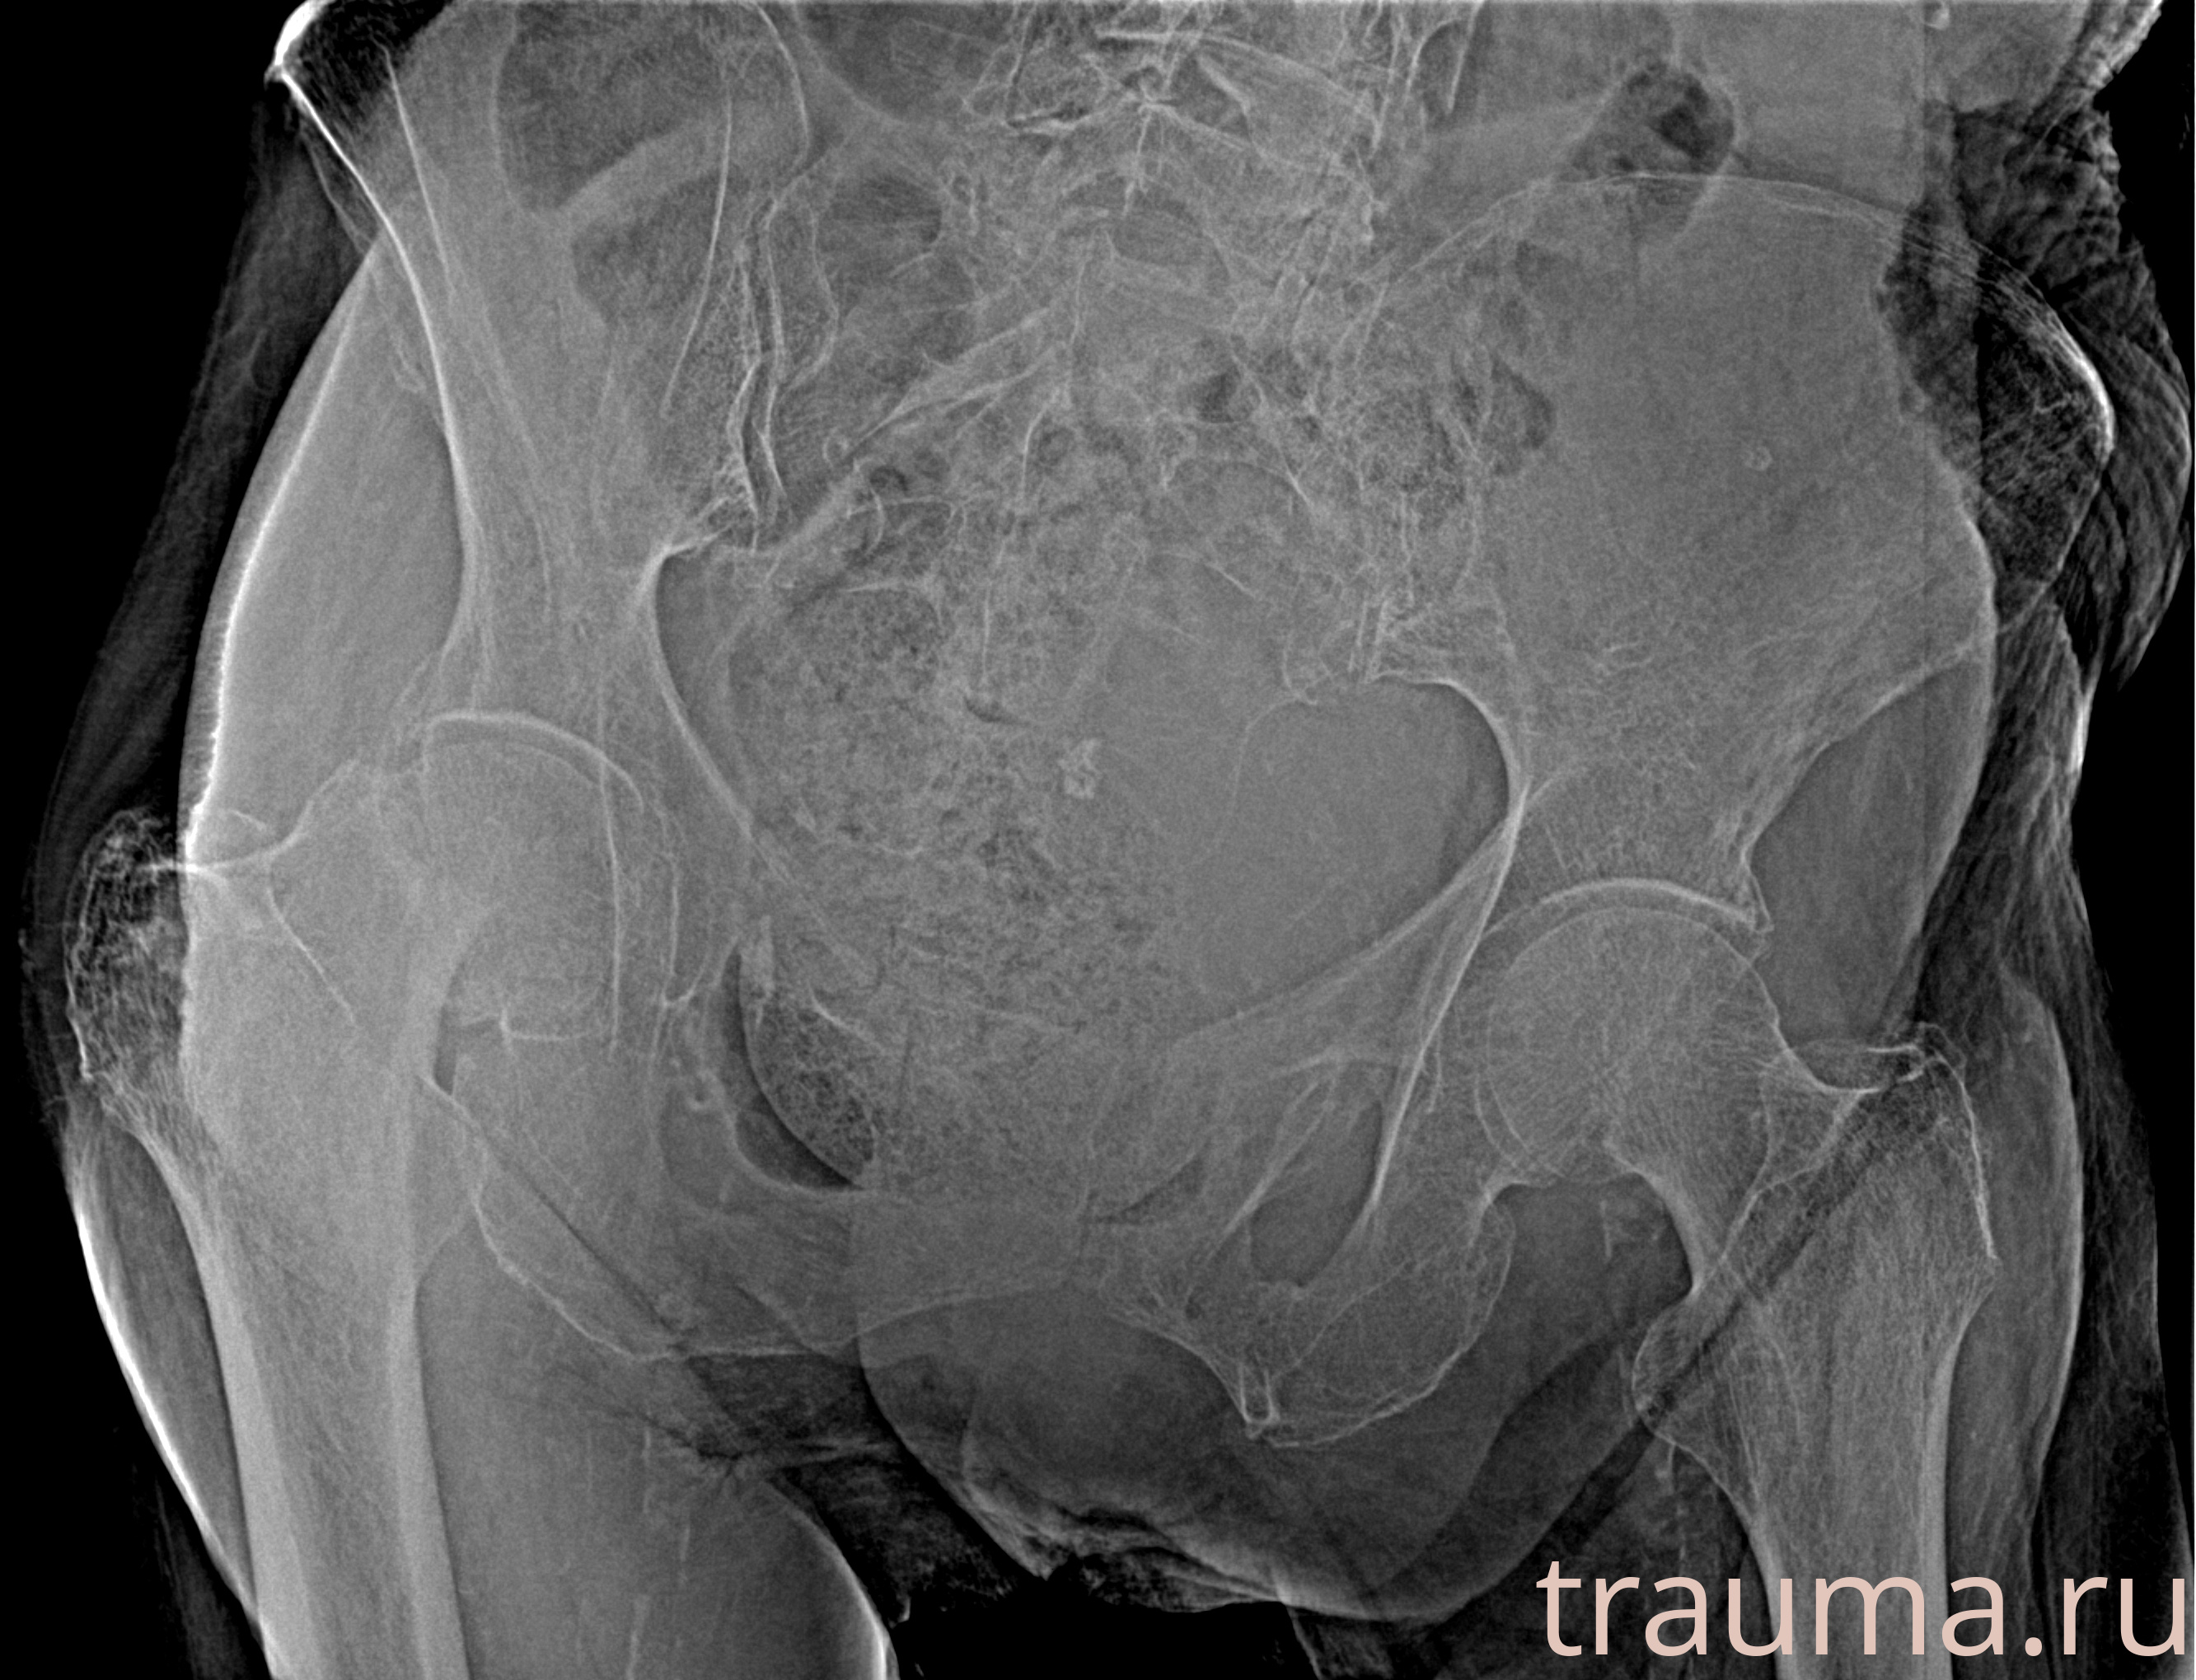

Рентгенограммы

Рентген на дому: по вашему адресу приезжает врач-рентгенолог, травматолог-ортопед с мобильным рентгеновским аппаратом, проводит диагностику травмы или заболевания, делает необходимые рентгенограммы, дает рекомендации по дальнейшему лечению. Получить качественные снимки в домашних условиях возможно благодаря уникальной методике, разработанной МосРентген Центром для института  Склифосовского